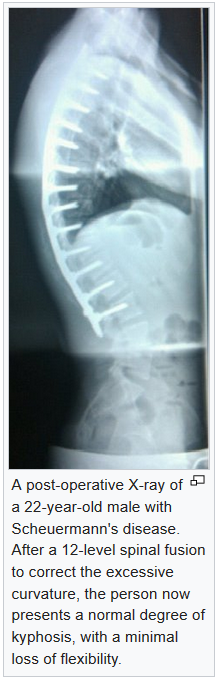

See our thoracic spine has a normal slight bend (medically termed as "kyphosis") but in Scheuermann's Kyphosis, it's much more (see image above). It refers to a condition that tends to happen moreso in one's adolescent (teenage) years, usually at the end of the growth years/age.

Most of the time, Scheuermann's kyphosis appears in the thoracic (ribcage vertebrae) which cannot be corrected naturally. Patients who suffer from Scheuermann's kyphosis will have a deep/big hump (medically termed as "gibbus") when they bend forward.

and shows no changes on x-ray, and its different from Scheuermann's kyphosis where it shows clearly on x-ray - the vertebral body will show a forward wedging with irregular and herniated discs.

where surgeon will straighten the spine using rods and screws (like scaffolding)

Surgery is the last resort if conservative treatment fails, or there is rapid worsening of the curve, or there is an imminent health risk like decreased lung function. The surgical procedure will involve the use of a set of titanium rods with screws on either side of the spine to achieve straightening of the spine.